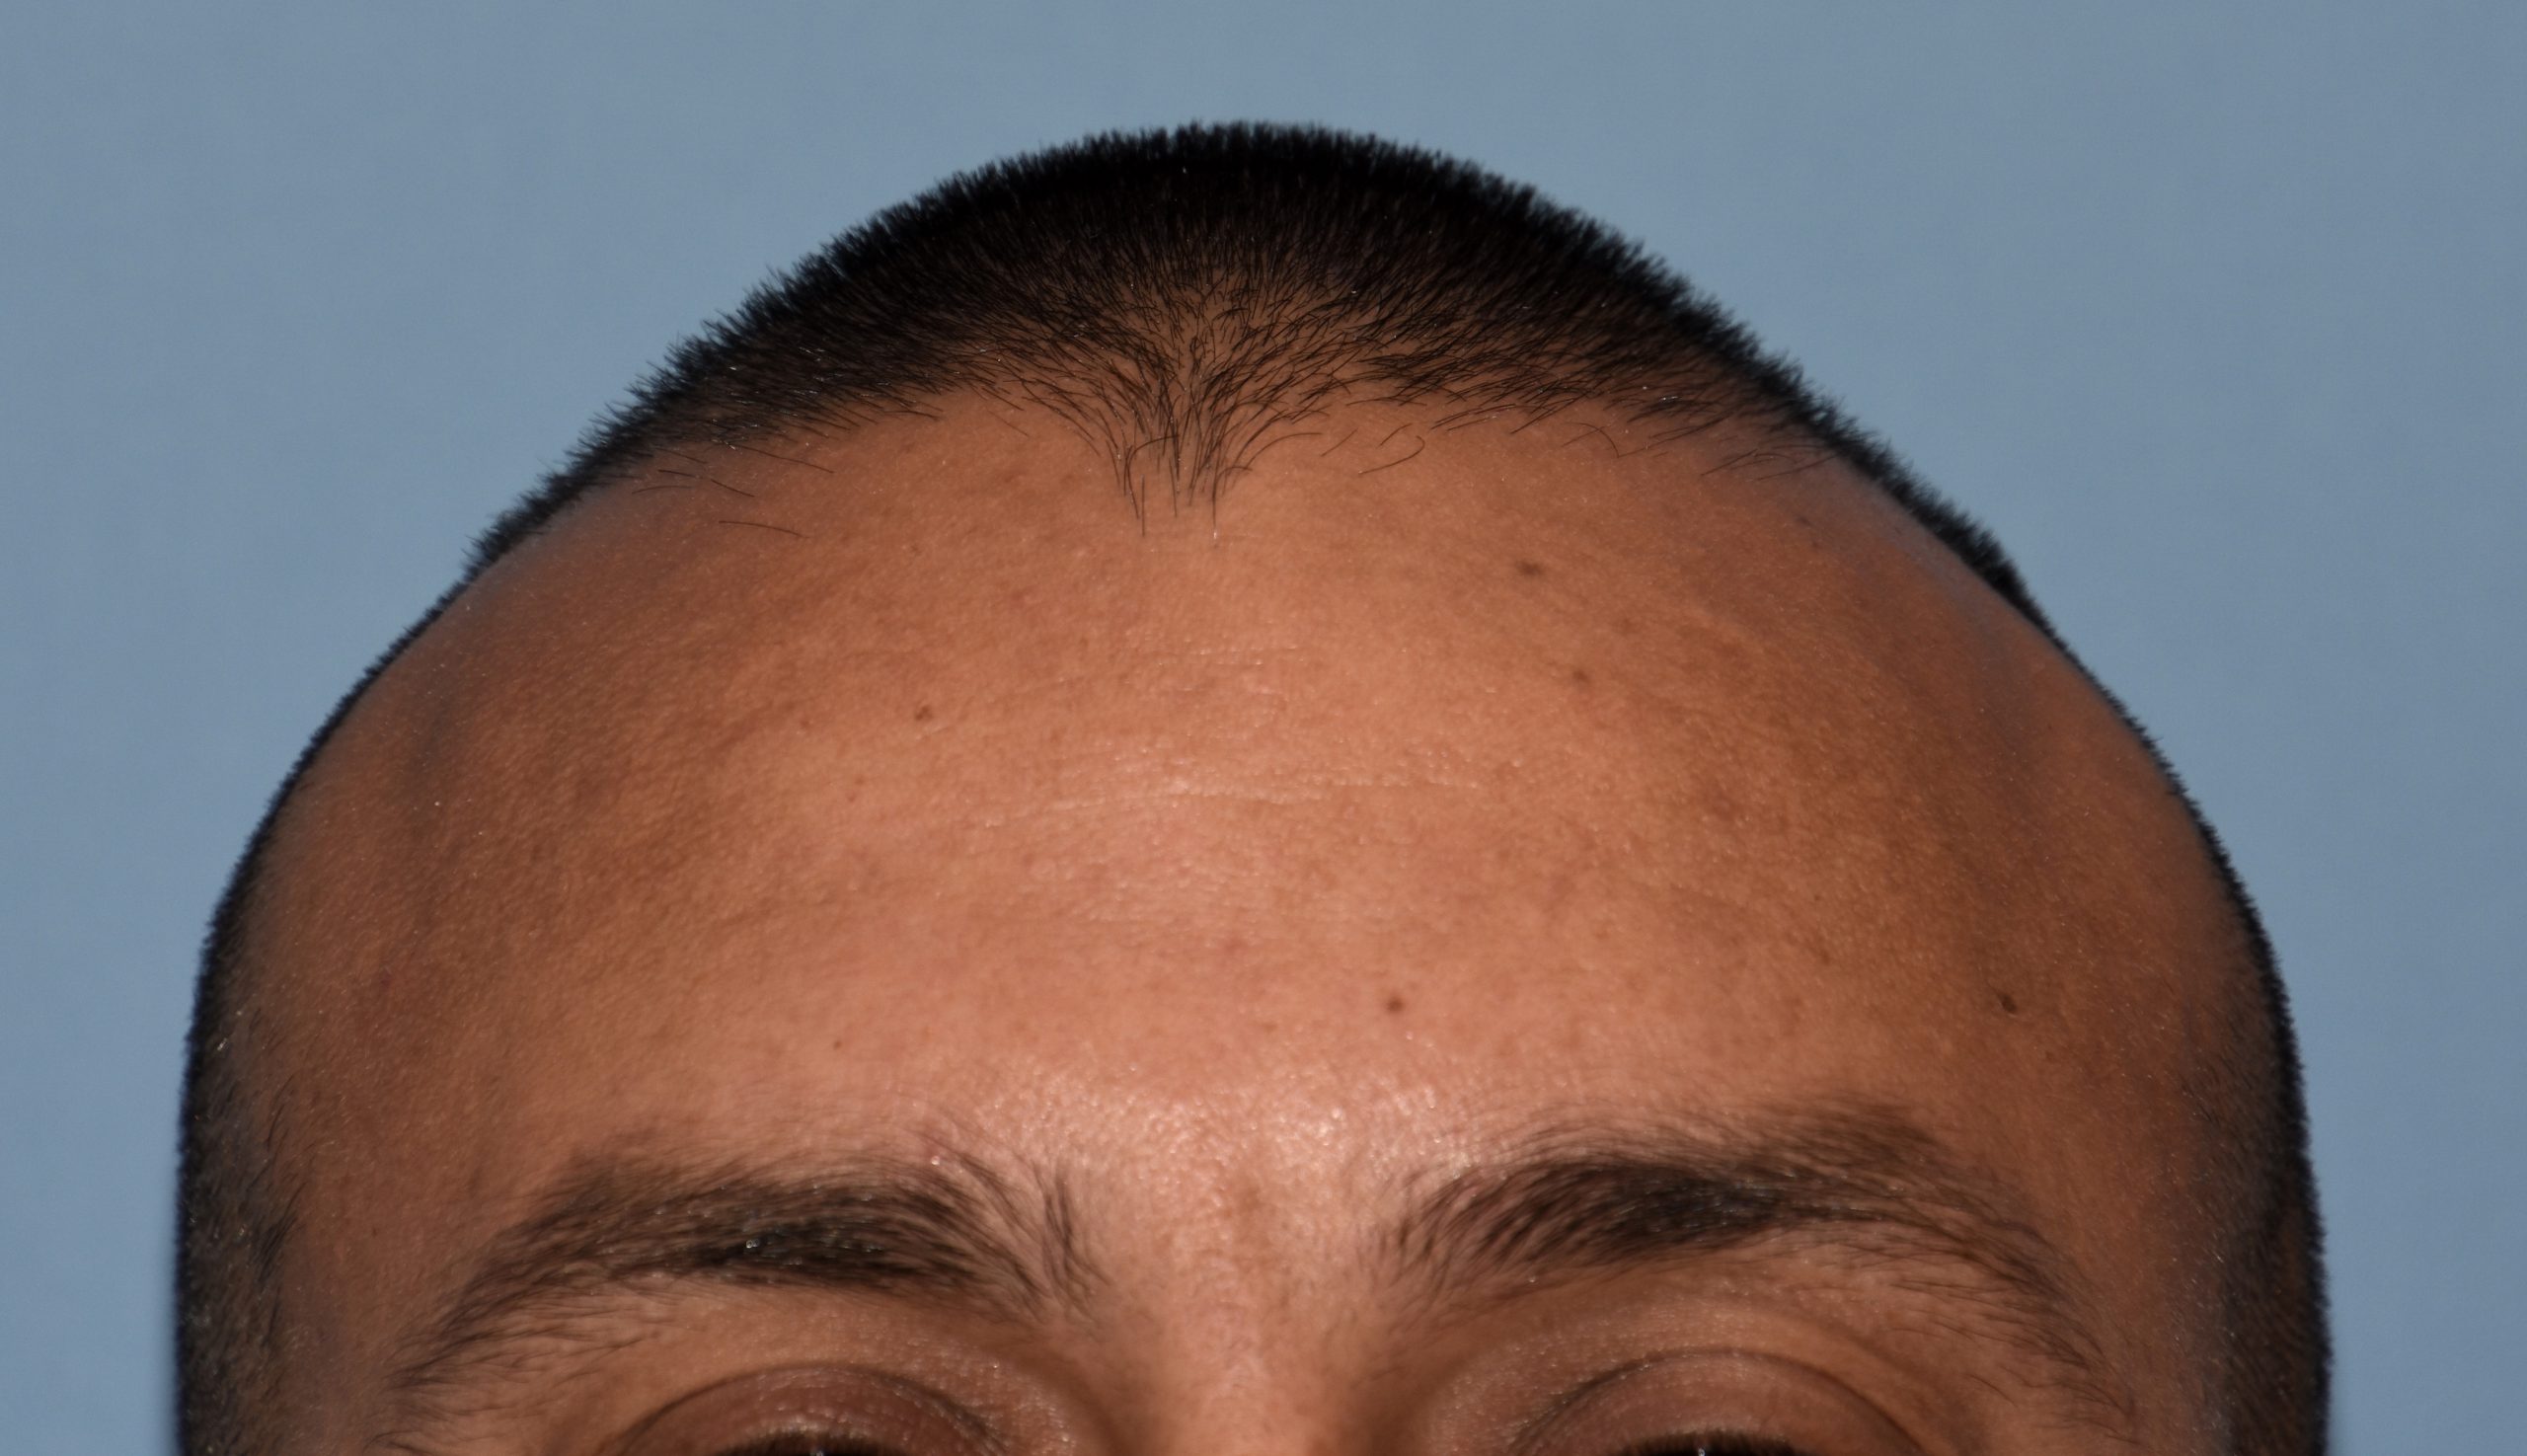

Patient 100

Desire for reshaping of an asymmetric flat back of the head in a shaved head male.

A combined back of the head reshaping procedure was done with a custom skull implant, sagittal ridge reduction and a right temporal muscle reduction.

Desire for reshaping of an asymmetric flat back of the head in a shaved head male.

A combined back of the head reshaping procedure was done with a custom skull implant, sagittal ridge reduction and a right temporal muscle reduction.